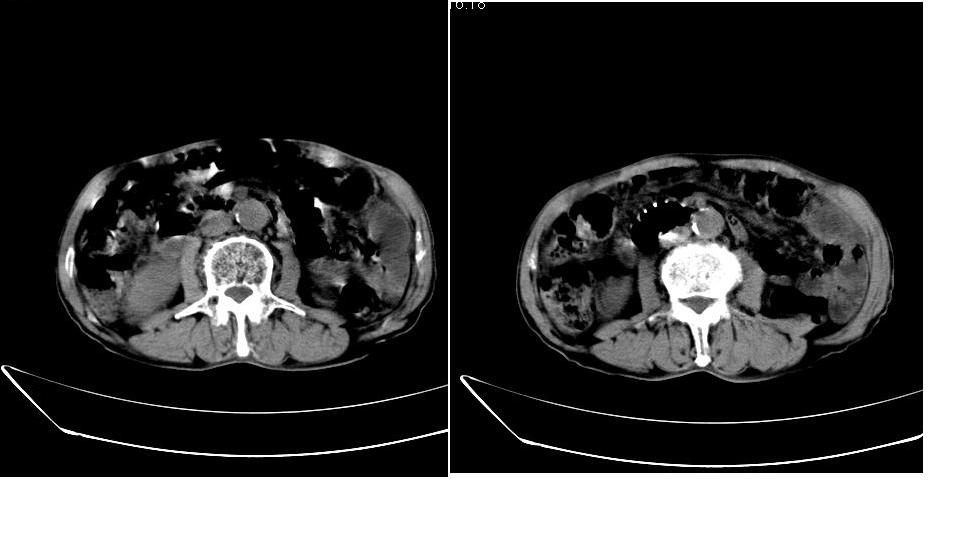

男,76岁,上腹部疼二天来就诊,彩超提示肝左叶占位,随后做上腹部ct平扫,今天做上腹部ct增强扫描,手工推药,效果不好,请谅解。

肝左叶s4肿块强化形式大概是:慢进慢出,逐渐强化----考虑血管瘤/腺瘤?{动脉期应更提前扫}。

1)肝右叶前段低密度灶,不排除肝癌可能;建议查afp。2)右肾上极囊肿。

肝内胆管积气扩张,胆囊增大,肝右前叶低密度灶,逐渐强化,一元论,胆系感染,局限性肝脓肿;右肾囊肿。

考虑肝s4段肝脓肿可能?未排除肝癌。右肾上极囊肿。